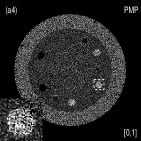

III.3 Catphan©600 phantom study

We acquired the Catphan©600 phantom data on a tabletop cone-beam CT (CBCT) system whose geometry matched that of a Varian On-Board Imager (OBI) on the Trilogy radiation therapy machine. We inserted iodine solutions with nominal concentrations of and into the phantom. There were pixels with a physical size of per pixel on the CB4030 flat-panel detector (Varian Medical Systems). The DECT measurements were obtained at kVp and kVp with a tube current of mA and a pulse width of ms. We acquired projections over in each scan. Using a fan-beam geometry with a longitudinal beam width of on the detector niu2010shading , We acquired projections with scatter contamination inherently suppressed. We used a contrast rod slice of the Catphan©600 phantom to evaluated the proposed method. We reconstructed attenuation images of size with a pixel size of . Fig. 3 shows the low- and high-energy CT images. Fig. 3(a) identifies the rods with labels: Teflon (labeled as ), Delrin (labeled as ), Iodine solution of (labeled as ), Polystyrene (labeled as ), low-density Polyethylene (LDPE) (labeled as ), Polymethylpentene (PMP) (labeled as ), Iodine solution of (labeled as ). Fig. 3(b) shows selected basis materials and ROIs in white dashed line circles: Teflon (ROI1), Delrin (ROI2), Iodine solution of (ROI3), PMP (ROI4), Inner soft tissue (ROI5) and Air (ROI6).

Fig. 4 shows the decomposed material images by the Direct Inversion, the PWLS-EP-LOOP and the PWLS-TNV- method. The left corners of the to the column of Fig. 4 show enlarged rods that are highlighted with white dashed boxes in decomposed material images. Table 2 summarizes the means and noise STDs of ROIs of decomposed basis material images. The volume fraction (VF) accuracies were , , and for the Direction Inversion, the PWLS-EP-LOOP and the PWLS-TNV- method, respectively. Compared with the Direct Inversion and the PWLS-EP-LOOP method, the proposed PWLS-TNV- method increases the VF accuracy by and respectively.

Table 3 summarizes the average electron densities of contrast rods and RMSE() of electron density for the three MMD methods. The RMSE() was , and for the Direct Inversion method, the PWLS-EP-LOOP method and the proposed PWLS-TNV- method, respectively. The proposed PWLS-TNV- method suppressed noise, decreases crosstalk and increased decomposition accuracy in the material images, while maintaining high image quality.